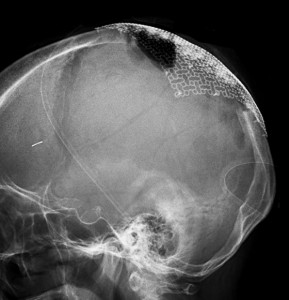

手術直後の画像です。全部いっぺんに摘出するのは無理なので,まず前から80%くらいの腫瘍を摘出しました。肥厚した骨はチタンプレートで置き換えてあります。後頭部の上矢状洞内と大脳鎌に少し残りましたが,この6ヶ月後に2回目の開頭術をして全摘出しました。結果的にこの例では,上矢状洞を冠状縫合のあたりから,静脈洞交会まで壁ごと全部摘出しましたが,脳浮腫も何も生じませんでした。腫瘍の両側にある皮質静脈 cortical veinsを損傷しないことが肝要です。

右の病理像は,頭蓋骨浸潤している部分 ですが,骨破壊は良性髄膜腫に特徴的な骨内浸潤像です。この骨浸潤像は悪性像とはいえません。MIB-1は高いところで8%、低いところで3%程度です。